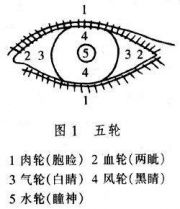

| 2021年7月26日 (一) 20:03 | 五轮.jpg (文件) |  |

25 KB | Uploaded with SimpleBatchUpload | 3 |